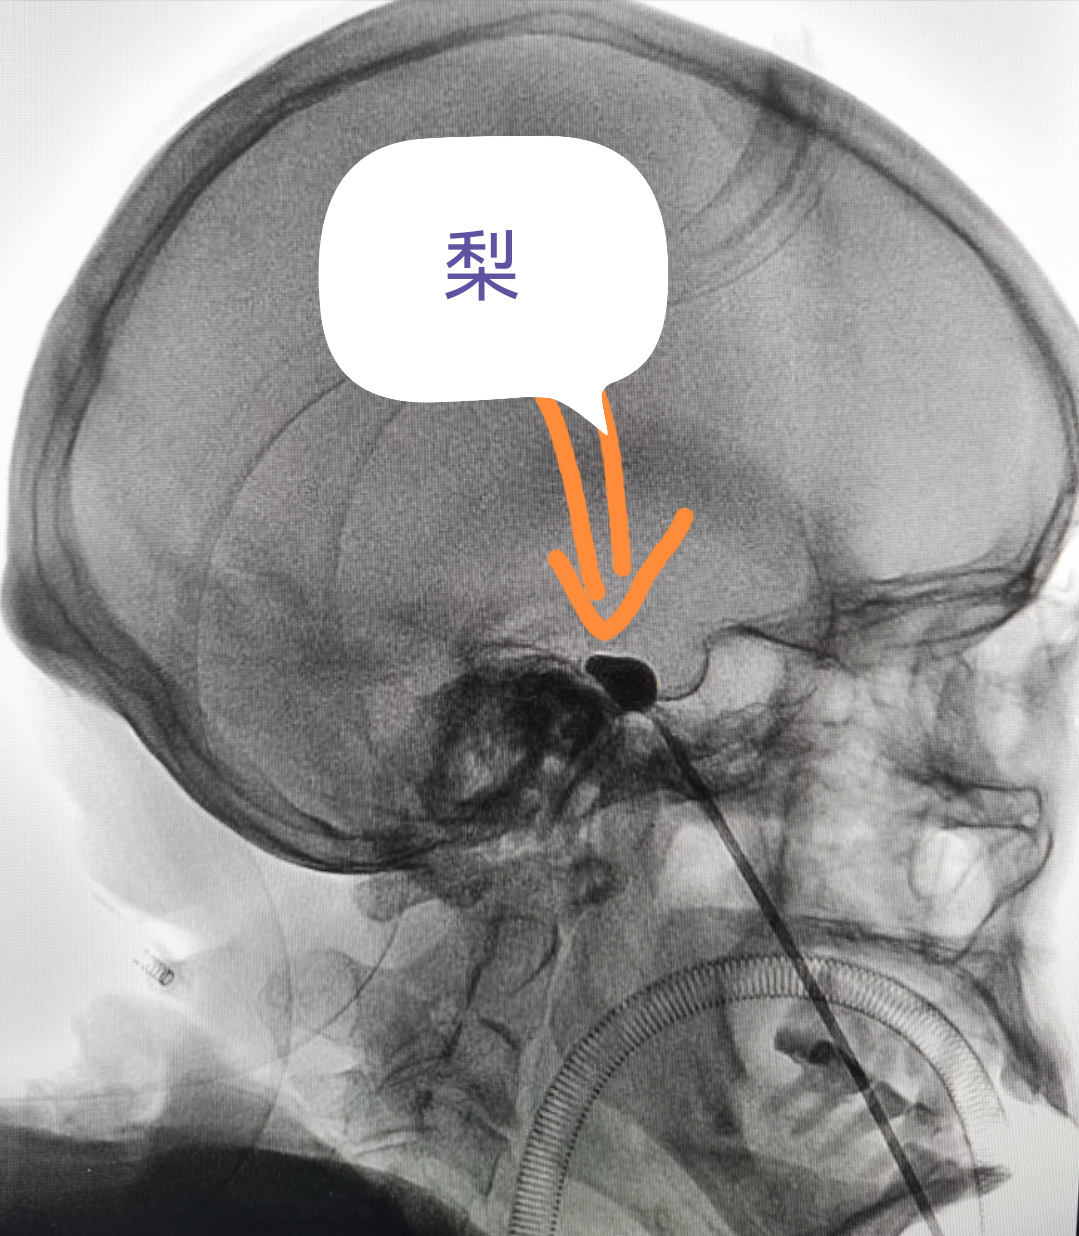

看到這個(gè)“梨”,你會(huì)想到什么?

專(zhuān)業(yè)醫(yī)生卻會(huì)說(shuō):ta和我們的

治療三叉神經(jīng)痛中微創(chuàng)技術(shù)在影像上的呈現(xiàn)挺像噠

(看著像梨,哈哈...)

經(jīng)過(guò)面部口角處穿刺到三叉神經(jīng)半月節(jié)內(nèi),放入球囊,向球囊里打入對(duì)比劑,使球囊擴(kuò)張,完美顯示一個(gè)“梨”形,壓迫3-5分鐘,壓迫毀損感覺(jué)神經(jīng),保留運(yùn)動(dòng)神經(jīng),阻斷疼痛信號(hào)傳導(dǎo),達(dá)到止痛目的。適合單支或多支發(fā)病患者,尤其高齡、合并癥多,不愿意接受開(kāi)顱手術(shù)患者。術(shù)后面部稍有麻木。